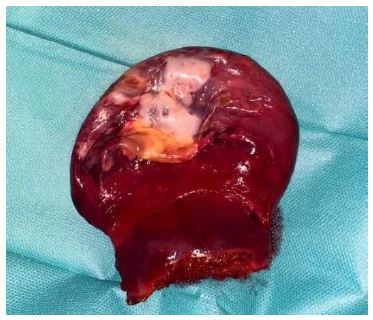

The surgical specimen (Figure 6) was extracted with an endobag through the 15 mm incision and a drainage was placed in the splenic bed. The postoperative period was uneventful. A CEUS was performed five days after surgery showing that the residual spleen maintained a normal perfusion of the parenchyma [7]. At 12-month follow up, CEUS confirmed the absence of recurrent splenic cysts and the normal perfusion of the remnant spleen (Figure 7).

The histological analysis showed the presence of one single cystic lesion; the immunohistochemical staining revealed the lymphatic origin of the cyst, confirming the diagnosis of splenic unilocular cystic lymphangioma.

Figure 6: The surgical piece: anterior surface of the upper splenic pole with the cystic lesion.